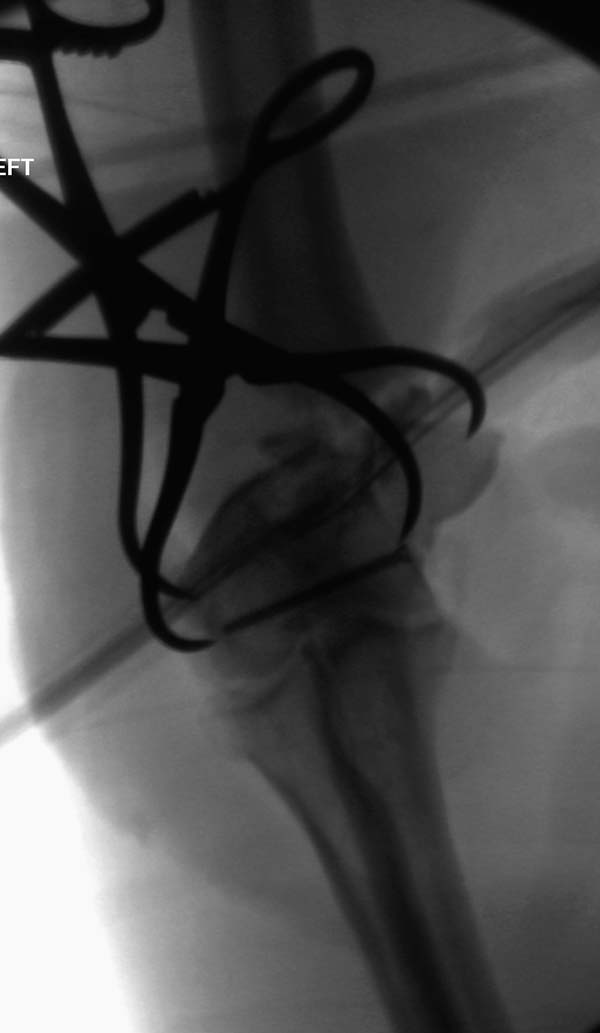

Из представленнего материала видно, что между снимками нет разницы. Отсутствует репозиция не только медиального, а также латерального мыщелка. На боковом снимке мыщелок расположен спереди, а прямом головка луча упирается в край мыщелка, что означает ротацию. Отсутствует компрессия между мыщелками, а один шуруп не смог удержать медиальную сторону, которая при первом же движении рассыпалось.

Ошибка в фиксации привела к дополнительным проблемам, теперь, кроме плеча, надо заниматься с локтевым отростком и невритом. Доступ обычно из двух сторон мышцы трицепса, но некоторым внутрисуставным переломам визуализацию можно создать за счет остеотомии локтевого отростка и как дружно заявили, что фиксацию заканчивает только по Веберу.